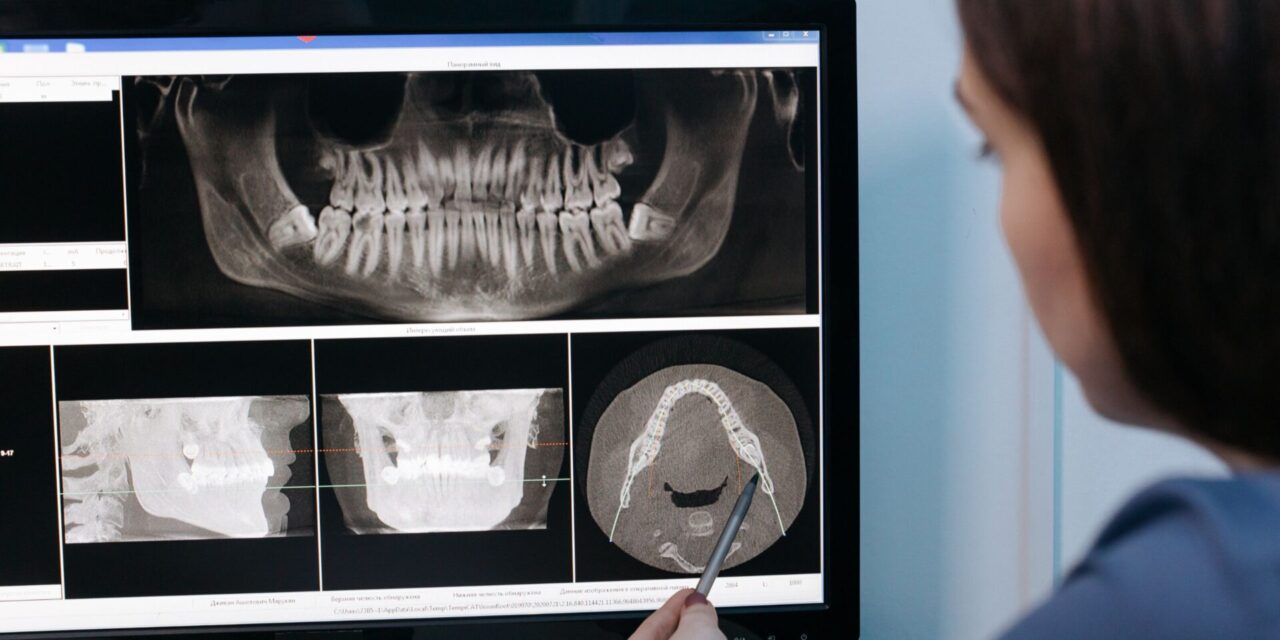

- Tomografía de haz cónico (CBCT): Es un tipo de radiografía que permite obtener imágenes tridimensionales de los dientes, los huesos de la mandíbula y las estructuras faciales. Esta tecnología es fundamental para un diagnóstico exhaustivo, especialmente en la planificación de cirugías complejas.